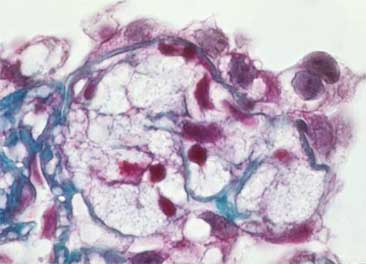

The characteristic histologic feature is sclerosis of segments of the glomerular tuft in some glomeruli (“segmental and focal”), with mesangial expansion and capillary lumen loss in these segments. The injury can be more notorious in the vascular pole or in the periphery of the tuft. When advancing the process the sclerosis becomes global and is indistinguishable of the secondary sclerosis to other diseases. The sclerosing segments are positive with PAS and silver-methenamine stains (type IV collagen). From the Fifties it is said that juxtamedullary glomeruli are more compromised by the segmental lesions. There are, in many cases, podocyte hypertrophy and hyperplasia, mainly on the surface of the sclerosed tuft segment (“cap lesion” or “cellular lesion”). Podocytes frequently appear with protein droplets and lipid resorption. The glomeruli without sclerosing lesions can appear normal or with increase of the mesangial cellularity and, sometimes, hypertrophic (glomerulomegaly).

Figure 1. Glomerular tuft segmental sclerosis in the superior half; segments in the inferior half display mesangium and capillary walls and lumens with conserved architecture. (Masson’s trichrome, X400).

In some cases the lesions do not have the aspect of sclerosis (healing by glomerular collagen) but appear as homogenous material: Hyaline deposits. They are constituted by crystalline, eosinophilic, PAS positive, and fuchsinophilic or blue with trichrome stains material; this material is similar to glomerular material found in diabetic nephropathy. This material is negative with silver stains, in contrast to sclerosed segments, and frequently it is accompanied by lipid vacuoles. This material probably represents accumulation of serum proteins. Hyaline lesions usually accompany sclerosing lesions, but there are cases in which all the lesions are hyaline. Although they seem to be different morphologic aspects from a same disease, could have a different physiopathogeny. Some authors, and thus we do, diagnose the cases without hyalinosis as: “FSGS” and those that have hyalinosis: “FSGS with hyalinosis”, in an attempt to differentiate morphologically these two patterns and to try to determine if there are clinical and/or etiopathogenic differences.

Figure 3. The hyaline segments are eosinophilic, with homogenous aspect (arrows); they are different to sclerosing segments, but they could correspond to lesions in different stage of evolution. (H&E, X400).

Figure 4. Segmental Hyalinosis with lipid vacuoles and reddish color with the trichrome stain (arrow). The adjacent tuft presents solidification, with diminution or loss of capillary lumens. (Mason’s trichrome, X400).